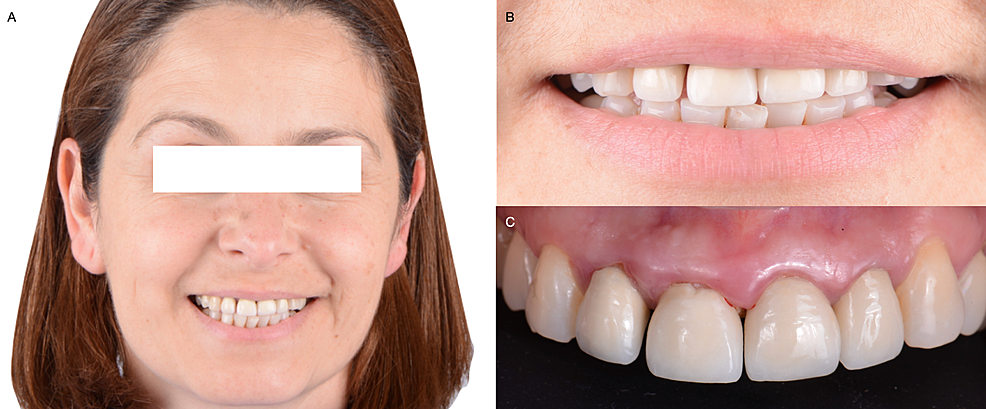

A 45-years-old female patient presented to the clinic with the chief complaint, “My front crowns are loose, and they come off sometimes”. The patient reported that she had crowns made of porcelain fused to metal placed on teeth from the maxillary right lateral incisor to the left incisor fifteen years ago (Figures 1). These crowns became loose and came off sometimes, which she previously cemented back on with an over-the-counter remedy from the pharmacy. The interdental papilla was reduced in height, forming a black triangle between anterior teeth.

After a detailed clinical evaluation, the maxillary right lateral incisor, central incisor, and maxillary left lateral incisor were diagnosed with mobility grade II. Incisal wear was found on the maxillary right and left canines. Radiographic evaluation showed the old crowns and metal posts on the maxillary left lateral incisor, central incisor, and right lateral incisor (Figure 2A). The patient had high esthetic demands and showed interest in having fixed all-ceramic restorations from the right maxillary canine to the left canine. Fortunately, the patient had a low smile line, and gingival inflammation and disharmony were not showing while smiling. The patient was informed of the need to remove the old crowns to re-assess the teeth’ clinical situation and agreed to the procedure.